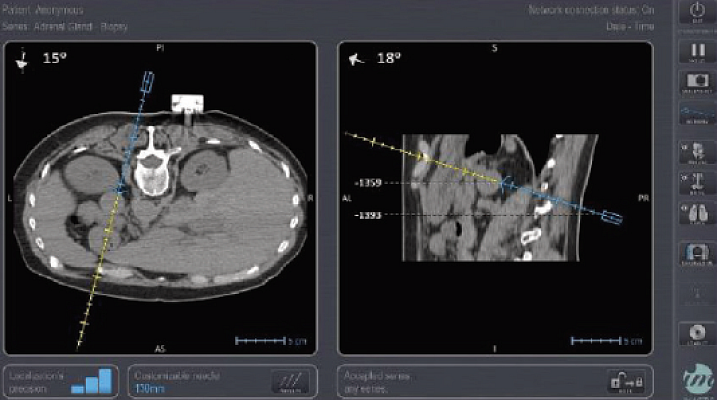

Imactis - CT navigace

Imactis je špičkový navigační systém, který optimalizuje intervenční radiologické procedury pomocí přesné CT navigace. Zásadně snižuje radiaci pro pacienta i personál a výrazně zkracuje dobu trvání zákroku, což vede k výrazné úspoře nákladů. Díky své přesnosti a efektivitě se stal klíčovým nástrojem v moderní medicíně.

• Radiologie hraje klíčovou roli v diagnostice a léčbě mnoha onemocnění. Využívá se pro dosažení cílových míst v lidském těle, ať už se jedná o orgány, cévy, nebo nádorové léze. Systém Imactis tento proces zjednodušuje a činí ho bezpečnějším. Díky přesnému navádění pomáhá efektivně optimalizovat každodenní procedury spojené s intervenční radiologií.

Proč je Imactis důležitý?

• Bezpečnost: Snížením počtu kontrolních snímků se snižuje radiace pro pacienta, lékaře i další personál až o 60 %. To zásadně zvyšuje bezpečnost každého zákroku.

• Přesnost: Systém zpřesňuje zaměření cílových míst až o 50 %. Díky tomu mohou lékaři provádět zákroky s maximální precizností a dosahovat lepších klinických výsledků.

• Úspora času a nákladů: Zkrácení doby trvání procedur a snížení potřeby opakovaných snímků vede k výrazné úspoře nákladů a času, což zvyšuje efektivitu zdravotnického pracoviště.

• Univerzální využití: Navigační systém Imactis nachází uplatnění nejen v intervenční radiologii. Je skvělým nástrojem pro výuku studentů medicíny, ale také v mnoha dalších oborech, které vyžadují přesné navádění v lidském těle.

• Snadná integrace: Systém lze snadno integrovat do stávajících CT pracovišť, což minimalizuje potřebu velkých investic do nového vybavení.

Díky všem těmto výhodám se Imactis stává nezbytnou součástí moderního lékařského vybavení, protože umožňuje efektivnější a bezpečnější přístup k léčbě a diagnostice řady onemocnění.